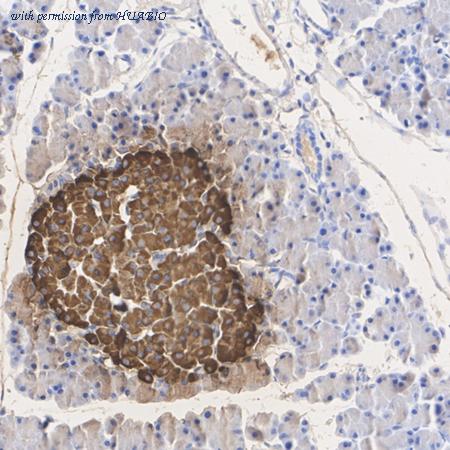

Immunohistochemical analysis of paraffin-embedded human pancreas tissue with Rabbit anti-Insulin B Chain antibody (0807-11) at 1/10,000 dilution. The section was pre-treated using heat mediated antigen retrieval with Tris-EDTA buffer (pH 9.0) for 20 minutes. The tissues were blocked in 1% BSA for 20 minutes at room temperature, washed with ddH2O and PBS, and then probed with the primary antibody (0807-11) at 1/10,000 dilution for 1 hour at room temperature. The detection was performed using an HRP conjugated compact polymer system. DAB was used as the chromogen. Tissues were counterstained with hematoxylin and mounted with DPX.

Immunohistochemical analysis of paraffin-embedded mouse pancreas tissue with Rabbit anti-Insulin B Chain antibody (0807-11) at 1/10,000 dilution. The section was pre-treated using heat mediated antigen retrieval with Tris-EDTA buffer (pH 9.0) for 20 minutes. The tissues were blocked in 1% BSA for 20 minutes at room temperature, washed with ddH2O and PBS, and then probed with the primary antibody (0807-11) at 1/10,000 dilution for 1 hour at room temperature. The detection was performed using an HRP conjugated compact polymer system. DAB was used as the chromogen. Tissues were counterstained with hematoxylin and mounted with DPX.

Immunohistochemical analysis of paraffin-embedded rat pancreas tissue with Rabbit anti-Insulin B Chain antibody (0807-11) at 1/2,000 dilution. The section was pre-treated using heat mediated antigen retrieval with Tris-EDTA buffer (pH 9.0) for 20 minutes. The tissues were blocked in 1% BSA for 20 minutes at room temperature, washed with ddH2O and PBS, and then probed with the primary antibody (0807-11) at 1/2,000 dilution for 1 hour at room temperature. The detection was performed using an HRP conjugated compact polymer system. DAB was used as the chromogen. Tissues were counterstained with hematoxylin and mounted with DPX.